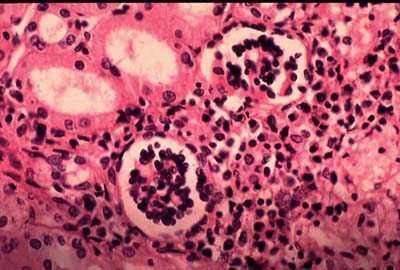

Висцеральный лейшманиоз может ограничиться кожными поражениями, но обычно в дальнейшем наступает генерализация процесса и развивается системный эндотелиоз с размножением паразитов в клетках гистофагоцитарной системы внутренних органов (селезёнки, печени, костного мозга, лимфатических, узлов, стенки кишечника, реже надпочечников, почек, лёгких и пр.). При этом наблюдается гиперплазия ретикулярной ткани, приводящая к увеличению паренхиматозных органов, особенно селезёнки.

По причине усиленной пролиферации эндотелиальных клеток отмечается атрофия пульпы селезёнки, зародышевых центров в лимфатических, узлах. Печёночные балки сдавливаются резко гипертрофированными купферовскими клетками. Наблюдается скопления макрофагов с большим количеством паразитов.

При данной болезни характерна последовательность клеточной реакции: в ранние сроки преобладает пролиферация гистиоцитов, на более поздних стадиях наблюдается лимфоплазмоцитарная инфильтрация. Могут возникать некротические очаги, инфаркты в селезёнке.